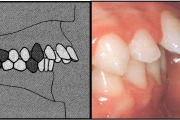

Normaalse jäävhammaskonna pilt küljelt ja eest vaadatuna.

prognaatne hambumus, ülemised eeshambad on ettepoole alumiste suhtes ja eest

progeenne hambumus; alumised eeshambad on ettepoole ülemiste suhtes;